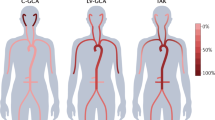

The evaluation of vasculitis by CMR may include angiography, vessel wall imaging and occasionally myocardial assessment (Figure 1, Table 1). The typical patient presenting with a vasculitis query to the CMR laboratory is one whose clinical, serological and even histopathological evaluations may have already led to diagnosis of a particular condition. For instance, a patient who initially presented with classic signs and symptoms of giant cell arteritis (GCA), underwent definitive temporal artery biopsy and received prednisone therapy, may subsequently be referred for CMR to define the extent of aortic involvement. Less commonly, the CMR laboratory is the first to propose vasculitis as a mechanism underlying the observed findings (Figure 2).

CMR provides a variety of techniques for noninvasive, three-dimensional imaging of the entire vascular tree that may be useful in patients with known or suspected vasculitis such as contrast-enhanced bright blood angiography. (A), noncontrast dark blood angiography (B and C, with lines indicating planes of reformatting of data from the 3D acquisition) and noncontrast bright blood angiography (D, shown in inverted grayscale).

Non-contrast approaches for angiography abound, starting with traditional time-of-flight (TOF) angiography. While infrequently relied upon for stenosis assessment in extracranial arteries, TOF angiography does provide complementary information to CE-MRA. Rapid, lower-resolution 3D TOF imaging prescribed over a large volume helps identify sites of disease for higher-resolution 2D dark blood scans for vessel wall imaging. Our laboratory and many others have found 3D navigator SSFP imaging to be tremendously useful for non-contrast bright blood MRA of the thoracic aorta [10], particularly when CE-MRA may not be feasible due to contraindications to gadolinium-based contrast administration. Similarly, 3D non-contrast dark blood MRA may be useful in certain settings, particularly when higher heart rate, greater field strength or other approaches help shorten what are typically longer scan times [11]. Dark blood imaging is also preferable when susceptibility artifact obscures interpretation of bright blood images. Another SSFP-based non-contrast approach that is particularly appealing for lower extremity imaging is non-enhanced quiescent-interval single-shot MR angiography (Figure 1) [12]. While initially developed for atherosclerosis imaging of the peripheral arteries, it warrants consideration in vasculitides where peripheral vascular involvement is not uncommon. Some of the more commonly used elements of the CMR vasculitis protocol are listed in Table 1. Table 2 suggests which segments of the arterial tree should be imaged in the most common primary vasculitides. Table 3 summarizes studies comparing magnetic resonance to other modalities commonly used to evaluate the inflammatory vasculitidies.